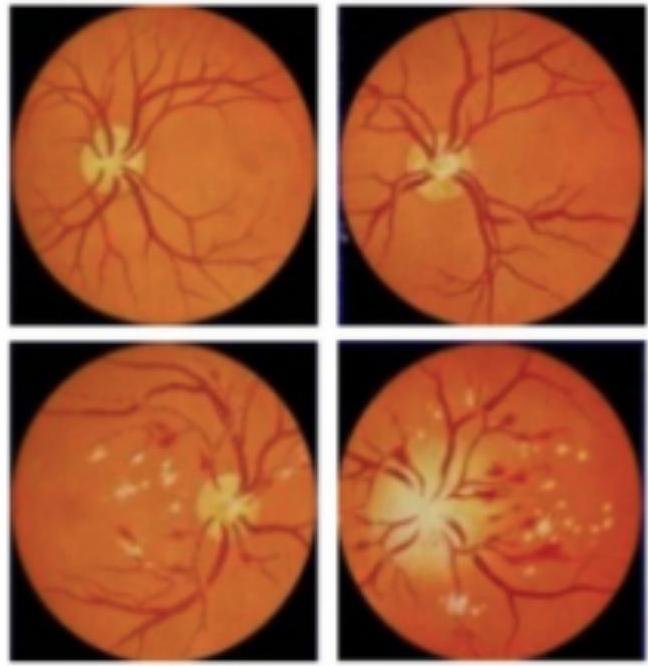

# HIPERTENSIÓN ARTERIAL ESENCIAL ## DEFINICIÓN Es un síndrome de etiología múltiple, caracterizado por la elevación persistente de las cifras de presión arterial a cifras >140 / 90 mmHg (de acuerdo a la **NOM-030**). Es producto de la resistencia vascular periférica y se traduce en daño vascular sistémico. ## EPIDEMIOLOGÍA - En México, su prevalencia es de 31.5% (en adultos obesos es mayor 42.3% que en IMC normal) - Existe una relación entre **HAS** y el excedente de peso. - El 47.3% de los pacientes desconocen que tienen esta enfermedad. - De los adultos con **HAS** diagnosticada por un médico, solo un 73.6% reciben tratamiento farmacológico y menos de la mitad de estos están bajo control. Es considerada como un predictor de morbimortalidad para enfermedades cardiovasculares como: - **EVC** - **EAP** - **IAM** - **IR** - **ICC** ## PROMOCIÓN A LA SALUD: - IMC 18.5 - 24.9 - Terapia de manejo de estrés - Consumo alto de frutas y vegetales - Abandono de hábito tabáquico - Ingesta baja de grasas saturadas - Reducción de sal en la dieta - Evitar consumo excesivo de cafeína | FACTORES MODIFICABLES | FACTORES NO MODIFICABLES | | :--------------------------- | :----------------------------------------------- | | - Tabaquismo | - Edad +45 años (el más importante) | | - Alcoholismo | - Masculino | | - Sobrepeso/Obesidad | - Raza Afroamericana | | - Sedentarismo | - Historia familiar (DM, HAS, EVC, Enfermedad | | - Dislipidemias | Coronaria) | | - Dieta rica en sal | | # EVALUACIÓN DE DAÑO A ÓRGANO BLANCO - Identificación de microalbuminuria: 30-300 mg / dL en EGO - Tasa de Filtrado Glomerular: 30-60 ml / min ## DETECCIÓN OPORTUNA Es conveniente realizar el escrutinio de la Hipertensión Arterial a través de la toma periódica de la misma mediante la estrategia oportuna en la consulta médica. El diagnóstico se establece tras dos mediciones de la presión arterial por consulta en al menos 2 citas continuas. ## DIAGNÓSTICO Se considera diagnóstico probable de **HAS** cuando exista elevación de la presión arterial con cifras iguales o mayores a 140/90 mmHg, registradas por personal capacitado. Si un paciente acude por datos de alarma o por urgencia hipertensiva, se diagnostica como **HAS** desde la primera consulta médica. También será diagnóstico si presenta desde la primera consulta cifras anormales y **DM** o daño a órgano blanco o insuficiencia renal moderada-grave (-60 ml / min). De acuerdo a la TA, se clasificarán en los siguientes: | CATEGORÍA | SISTÓLICA | DIASTÓLICA | | :------------------------------ | :------------ | :----------- | | ÓPTIMA | Menor a 120 | Menor a 80 | | NORMAL | 120-129 | 80-84 | | NORMAL ALTA | 130-139 | 85-89 | | HTA GRADO 1 | 140-159 | 90-99 | | HTA GRADO 2 | 160-179 | 100-109 | | HTA GRADO 3 | +180 | +110 | | Hipertensión Sistólica Aislada | +140 | Menor a 90 | Establecer el diagnóstico de **HAS** en la segunda consulta médica (al mes de la primera determinación) cuando se manifieste lo siguiente: - TA >140 / 90 mmHg - Bitácora positiva (registro de presión arterial en su domicilio) - Ambas situaciones Se recomienda usar el monitoreo de Holter cuando existe discordancia de presión arterial registrada en casa y la obtenida en el consultorio. # EVALUACIÓN CLÍNICA - Peso - Circunferencia de cintura - Talla - IMC ## EXPLORACIÓN FÍSICA - Auscultación carotídea, corazón y arterias renales - Búsqueda de soplos - Búsqueda de pulsos irregulares (FA) ## ESTUDIOS COMPLEMENTARIOS Se deberán realizar para estudio de la enfermedad y búsqueda de daño a órgano blanco, así como identificar comorbilidades: - Biometría Hemática - Química sanguínea - Electrolitos séricos - Perfil de lípidos - EGO - ECG ## PRUEBAS ESPECÍFICAS PARA DOB: - HbA1c - Proteinuria cuantitativa - Monitoreo Holter - USG Vascular, renal - Fundoscopía # TRATAMIENTO FARMACOLÓGICO ## INDICACIONES - El tratamiento farmacológico reduce el RCV y EVC, así como la muerte del paciente. - Iniciar tratamiento farmacológico cuando la TA es > 160/100 mmHg sin DOB ni otros factores. (no es necesario esperar una segunda medición). - Iniciar antihipertensivo INMEDIATO cuando la TA es >180/110 mmHg con cualquier nivel de RCV. ## 1ra elección: MONOTERAPIA CON ALGUNO DE LOS SIGUIENTES - **DIURÉTICOS TIAZÍDICOS** (Hidroclorotiazida o Clortalidona) - recomendado de primera instancia en todos sin condición especial. (contraindicados en **GOTA**) - **Beta-Bloqueadores** (Propanolol, Metoprolol) - **IECA** (Captopril, Enalapril) - VIGILAR POTASIO (K) SÉRICO porque reducen Angiotensina II y por tanto, Aldosterona. Cuando la Aldosterona funciona bien, elimina Hidrogeniones y Potasio, cuando no funciona, provoca **HIPERKALEMIA** con síntomas como hormigueo y calambres. - **ARA-II** (Losartán) - **Calcio-Antagonistas de acción Prolongada** (Nifedipino, Amlodipino) EFECTOS ADVERSOS: Edema, rubor, cefalea, taquicardia. Se recomienda iniciarlos a dosis bajas e incrementar gradualmente, dependiendo de la respuesta y el control de la TA. ## 2da elección: COMBINACIÓN DE 2 O MÁS FÁRMACOS DE PRIMERA LÍNEA Antes de agregar un segundo fármaco se debe usar el primero a dosis máxima. Combinación de 3 fármacos: - Tiazidas - **IECA** o **ARAII** NO COMBINAR IECA Y ARA-II - Calcio Antagonistas 1ra elección: **DIURÉTICOS TIAZIDAS**, **CALCIO-ANTAGONISTAS AP** O **ARA-II**. Si es de difícil control, se sugiere combinar 2 fármacos de primera línea. ## HIPERTENSIÓN RESISTENTE Se considera el uso de **ESPIRONOLACTONA** 25mg cada 24 horas Si hay poca tolerancia o contraindicaciones - Alfa o Beta-Bloqueadores. **HIPERTROFIA VENTRÍCULO IZQUIERDO** - Los Calcio Antagonistas tienen efectividad para reducirla. En los pacientes ancianos con PAS > 160 mmHg se recomienda iniciar tratamiento farmacológico. # META TA EN ADULTOS MENORES DE 60 AÑOS CON HAS SIN DIABETES NI IRCR # META TAS = 140 mmHg - No existe evidencia de beneficio de bajar aún más la TAS. ## META TAD = no menor a 65 mmHg - Por el riesgo de hipoperfusión coronaria. ## 1ra elección: MONOTERAPIA CON UNO DE LOS SIGUIENTES: - Diuréticos Tiazídicos (Hidroclorotiazida o Clortalidona) - NO INCLUIR BETABLOQUEADORES (riesgo **EVC**) - **IECA** (Captopril, Enalapril) - **ARA-II** (Losartán) - **Calcio-Antagonistas de acción Prolongada** (Nifedipino, Amlodipino) - Iniciar a dosis bajas e incrementos graduales dependiendo de la respuesta - Mantener vigilancia intencionada al fenómeno de hipotensión ortostática. 2da elección: TERAPIA CON 2 ANTIHIPERTENSIVOS DE PRIMERA LÍNEA Si persiste descontrol hipertensivo luego de alcanzar la dosis máxima tolerada. 3ra elección: ADICIONAR UN TERCER FÁRMACO DE PRIMERA LÍNEA FALLA TERAPÉUTICA CON 3 FÁRMACOS: Buscar las siguientes causas: - Pobre adherencia al tratamiento - Sobrecarga de volumen diastólico - Interacciones farmacológicas - Condiciones asociadas (obesidad, tabaquismo, alcohol, resistencia a insulina, pseudoresistencia al tratamiento) 1ra elección: Diuréticos y Calcio-Antagonistas. Iniciar tratamiento cuando la PAS >140 mmHg # META TA EN ADULTOS CON HIPERTENSIÓN ARTERIAL Y DIABETES TIPO 2: MENOR 130 / 80 mmHg ## 1ra elección: Monoterapia en el siguiente orden de preferencia: 1. **IECA** o **ARA-II** (los más recomendados en **DM2**) 2. Calcio Antagonistas 3. Tiazidas a dosis baja. - En pacientes con proteinuria o microalbuminuria se prefiere **ARA II**. 2da elección: Terapia Combinada: **IECA** o **ARA** (especialmente en DM con proteinuria o Microalbuminuria) Calcioantagonistas de efecto prolongado ## META TA EN ADULTOS CON HAS E IRC: MENOR 130 / 80 mmHg ## META TA EN ADULTOS MAYORES DE 60 AÑOS CON HAS SIN DIABETES O IRC Medidas Generales: Bajar de peso y programa de ejercicios aeróbicos. ## Terapia combinada: - **IECA** o **ARA II** - Calcio Antagonistas de efecto prolongado - Diuréticos ahorradores de K (Espironolactona) # TABLA DE VIDA SALUDABLE - Cambios en estilo de vida son la piedra angular del tratamiento. - Retrasará la progresión de la enfermedad. ## RESTRICCIÓN DE SODIO - Menos de 5 gramos al día, reduce la PAS en 4-5 mmHg con HAS y 1-2 mmHg en pacientes sin HAS. RECOMENDACIONES DE CONSUMO DE SODIO PARA PACIENTES CON HAS POR EDAD: | | CONSUMO RECOMENDADO | | :------------ | :------------------ | | MENORES DE 50 AÑOS | 1,500 mg / día | | DE 51 A 70 AÑOS | 1,300 mg / día | | MAYORES DE 70 AÑOS | 1,200 mg / día | ## PÉRDIDA DE PESO La dieta saludable y baja en calorías tiene un efecto modesto para la reducción de TA. La reducción del sobrepeso está ligada a la disminución de la TA Una reducción de 5 Kg de peso corporal disminuye en promedio 4.4 mmHg PAS y 3.6 mmHg de PAD. - Se recomienda lograr un IMC de 25. 1. Dieta rica en frutas y verduras, baja en grasas saturadas y totales disminuye 8-14 mmHg TA. 2. Escoger comidas con poca sal, vegetales sin sal adicionada, aves frescas, pescados y res sin grasa. 3. Evitar abundancia de sodio y alimentos curados como jamón o tocino. 4. Limitar consumo de salsas de soya, inglesa, cátsup o mostaza. 5. Las frutas frescas se recomiendan 4 -5 al día (evitar abuso por carbohidratos que promueven ganar peso). # CLASIFICACIÓN DE LA RETINOPATÍA HIPERTENSIVA  Keith - Wagener - Barker (1939) I Tortuosidad arterial y espasmo arterial localizado II Espasmo arteriolar generalizado II que produce cambios en los cruces AV III Hemorragias o exudados IV Edema de papila